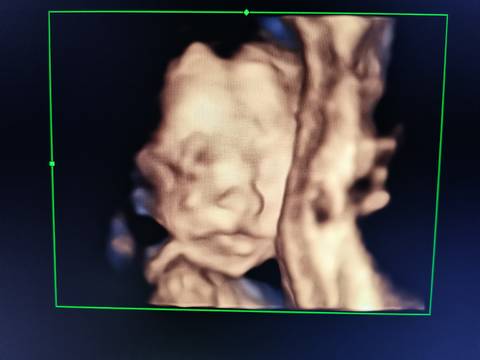

五个月宝宝这样正常吗?

journal_insert_pic_1684206114journal_insert_pic_1684206124

亲爱的,应该是很正常的呀,其实这个图片看的不是很准确的呀,只要医生描述的是好的就行了呀。

从图片上面的人不能判断什么问题,只要上面文字表达结果正常是没有任何问题的

这个是正常的,也没有什么关系的哦,然后你看下检查的一个描述正常就行